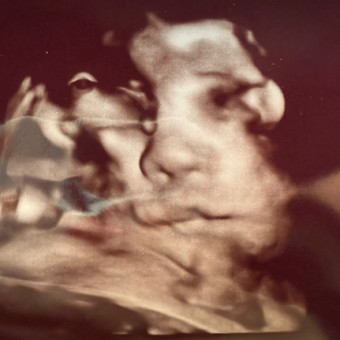

Diana and Carlos Baby Registry

Diana & Carlos Magana

Riverside, CA

January 6, 2026